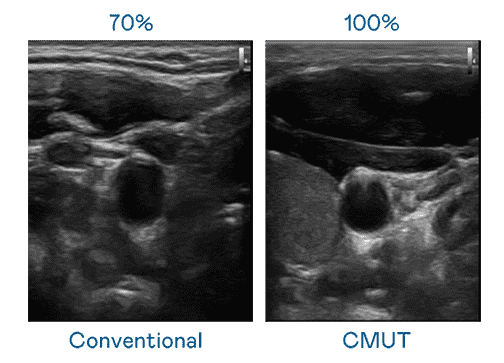

CMUT 技术是一种用电容式微机电元件来产生超音波讯号的技术。。与传统 PZT 压电式技术相比,,CMUT 频宽增加 30%,,,更宽频的超音波讯号让影像解析度大幅提升,,是实现高影像品质医疗超音波扫描、、、、促进精准医疗发展的关键技术。。。

大频宽带来超清晰影像

超音波影像的解析度高低,,首先取决于探头能发出的讯号频宽。。尊龙集团 CMUT 可提供高清晰的超音波讯号,,,,提供高频宽、、、、高灵敏度、、、影像纹理细节更高的超音波影像,,,,协助医护人员缩短影像判读时间及利用精准的医疗影像进行诊断。。